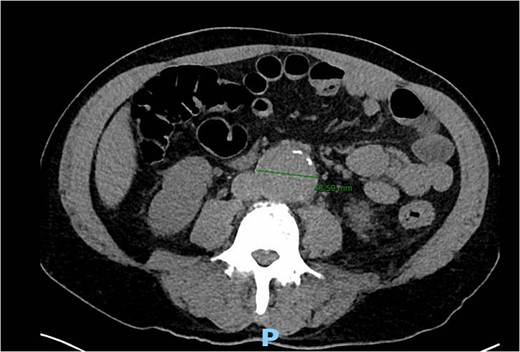

A 56-year-old male with no reported past medical history and a 70 pack year smoking history presented with a chief complaint of lower abdominal pain and body aches. On presentation, the patients white blood cell count (WBC) was 39.6 and procalcitonin was 43.4. Blood cultures were drawn and demonstrated P. mirabilis bacteremia. Computed tomography (CT) abdomen/pelvis was performed as well as ultrasound (US) of scrotum demonstrating a complex fluid collection within scrotal sac that was determined to be a scrotal wall abscess. The patient was started on a course of Unasyn and Urology promptly took him to the operating room (OR) for incision and drainage. Vascular surgery was consulted due to an incidental finding of an abdominal aortic aneurysm on CT measuring 4.7 × 4.6 cm (Figs 1 and 2). The patient was evaluated by the vascular surgery team following his urological procedure and denied any history of abdominal pain or back pain. Physical exam was largely unremarkable however the patient’s bilateral toes were noted to have blue discoloration with motor and sensation intact. Outpatient follow up with routine US scans for the AAA was recommended. Ankle brachial index (ABI) as well as an echocardiography was ordered to further work up the patient’s dusky toes. On Day 2 of hospitalization, ABIs returned showing severe peripheral vascular disease (PVD) and the echocardiography ruled out endocarditis. At this time an angiogram was planned to further the patient’s PVD workup however this was deferred as the patient remained septic with a WBC of 30. Over the course of the next few days the patient refused antibiotics and remained septic with a WBC in the 20s. At this time his toes quickly deteriorated from dusky to dry gangrene. On Day 8 of hospitalization the patient remained septic and was now complaining of new onset mid-abdominal pain. Emergent CT showed AAA was now 7.7 × 7.8 cm with periaortic fat stranding concerning for impending rupture (Figs 3 and 4). The patient was taken emergently to the OR for open repair. Upon visualization, the abdominal aortic aneurysm was clearly infected with signs of impending rupture on the left lateral wall and purulent material including infected thrombus. Tissue was cultured however showed no growth, likely due to the fact that the patient had been on antibiotic therapy for a week at this time. Reconstruction with an aorto-biiliac bypass using rifampin-soaked dacron graft was performed. A piece of omentum was mobilized over the graft and the retroperitoneum was closed over it. The abdomen was left open for a return to the OR for a second look which showed no concerns for bowel ischemia, worsening infection or bleeding. On post-op Day 5 the patient was extubated, off pressor support, and transferred to the floor. The patient’s postoperative course was unremarkable except for bilateral toes demarcating to dry gangrene.

Frontal CT of the abdomen and pelvis demonstrating 4.79 cm AAA.